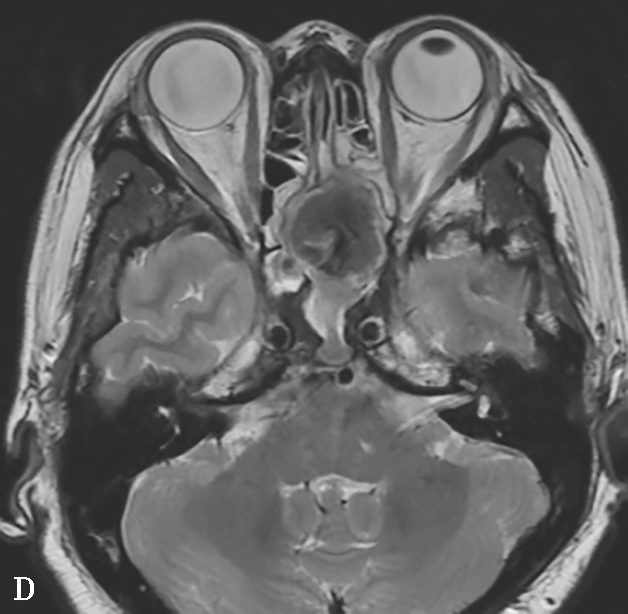

4.CT表现

①平扫表现:病变窦腔黏膜增厚,或可见形态不规则、中等密度的软组织影,病灶范围广泛时常伴坏死而表现为密度不均匀,病变内高密度影提示真菌感染。受累窦壁骨质膨胀,呈局灶性不规则破坏,伴或不伴骨硬化。病变窦腔周围脂肪间隙受累模糊,邻近窦壁骨质也可正常,这是因为病变的播散是通过血管周围间隙的蔓延,邻近间隙受累血管充血水肿或软组织内真菌浸润导致(图1-3-25A、B)。②增强扫描表现:病变窦腔周围脂肪组织和邻近肌肉可见中等强化。对蝶窦CIFRS进一步行CT血管造影有助于明确有无邻近动脉狭窄或闭塞;确定缺血区域的范围;识别假性动脉瘤。

5.MRI表现

①T 1 WI表现:由于蛋白质和水的比例不同,伴真菌成分的出现,T 2 WI信号表现多种多样,与脑灰质信号相比,多数呈低或等信号,病变窦腔周围脂肪信号减低。②T 2 WI表现:根据病程长短、病灶有无出血和坏死灶,病变T 2 WI信号也多种多样,多呈高-等低混杂信号,以低信号为主;高信号由病灶出血,积液造成,而等信号则由于病灶内肉芽肿形成,T 2 WI明显低信号由病灶内的菌丝或纤维化造成。病变窦腔受累脂肪间隙信号减低,抑脂像有助于判断有无脂肪浸润及浸润范围。③弥散加权像:扩散明显受限,ADC(表观弥散系数)图呈明显低信号,主要是因为病灶以真菌菌丝及纤维基质为主,内含假性结核肉芽肿结节及大量的坏死渗出,从而抑制水分子的弥散。④MRA:可显示血管有无受累(狭窄、夹层、血栓形成)。⑤增强扫描表现:病灶呈明显不均匀强化(图1-3-25C~F)。

图1-3-25 慢性侵袭性真菌性鼻窦炎

A、B.横断面CT及冠状面CT骨窗,示右侧蝶窦可见软组织影充填,蝶窦侧壁欠光整,骨皮质略模糊;C.横断面T 2 WI,示右侧蝶窦病变呈混杂等略低信号,右侧海绵窦受累增厚;D.横断面T 1 WI,示病变呈略高信号;E.横断面T 1 WI+FS+C,示蝶窦腔病变大部分无强化,可见不规则索条状明显强化影,窦腔边缘黏膜增厚强化,右侧海绵窦受累增厚强化,斜坡及Meckel腔脑膜增厚强化;F.冠状面T 1 WI+FS+C,示蝶窦病变破坏鞍底骨质,累及鞍上及右侧海绵窦,垂体受累轻到中度不均匀强化,蝶窦黏膜弥漫性增厚强化